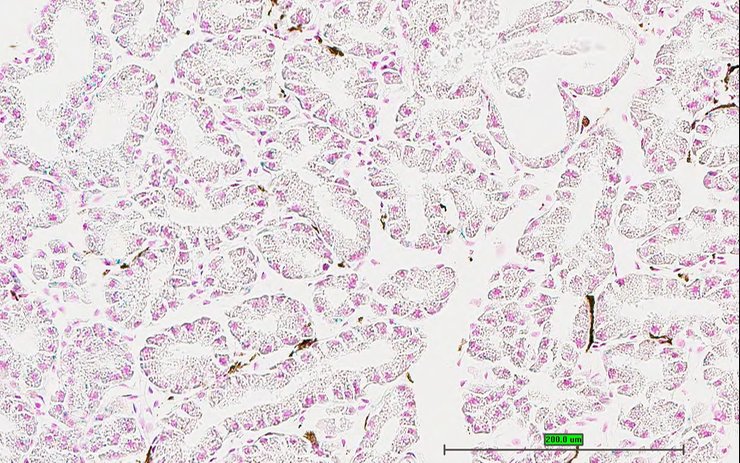

Specimen UC Davis_1870088: postnatal adult; Atf6btm1.1(KOMP)Vlcg/Atf6b+ (more )

Structure Level Pattern Image Note

TS28: lung Present UC Davis_1870088

Specimen UC Davis_1870089: postnatal adult; Atf6btm1.1(KOMP)Vlcg/Atf6b+ (more )

TS28: lung Present UC Davis_1870089

Specimen UC Davis_1870144: postnatal adult; Atf6btm1.1(KOMP)Vlcg/Atf6b+ (more )

TS28: lung Present UC Davis_1870144

Specimen UC Davis_1870145: postnatal adult; Atf6btm1.1(KOMP)Vlcg/Atf6b+ (more )

TS28: lung Present UC Davis_1870145